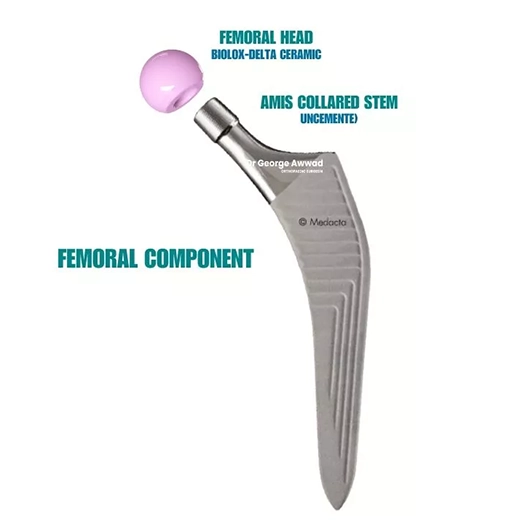

Types of hip implants used in total hip replacement

During a total hip replacement, the damaged parts of the hip joint are replaced with prosthetic components designed to restore function, reduce pain, and support long-term mobility. Dr Awwad selects each implant based on your unique anatomy, lifestyle, and long-term goals.

Main components of a hip replacement

A typical total hip replacement involves three key components:

- Acetabular cup – This replaces the hip socket. It is usually made of a strong metal and contains a smooth inner liner made of polyethylene or ceramic, allowing the joint to move freely.

- Femoral stem– Inserted into the thigh bone (femur), this metal component provides the foundation for the artificial joint. Stems come in various shapes and sizes to match the patient’s bone structure.

- Femoral head – The ball component fits into the socket and mimics the natural head of the femur. It may be made of ceramic or metal, depending on individual needs.

Implant fixation: Cemented vs uncemented

Dr Awwad uses either cemented, uncemented, or hybrid fixation methods based on your bone quality and health profile:

- Cemented implants are held in place with bone cement and are often used in patients with softer bone or lower bone density.

- Uncemented implants have a porous surface that encourages natural bone growth into the implant (known as osseointegration), offering a biological bond over time. These are often used in younger, active patients with good bone quality.

Implant system: The AMIS femoral stem

For most anterior approach hip replacements, Dr Awwad uses the AMIS femoral stem, a prosthesis designed specifically for minimally invasive surgery. This stem supports a secure fit in the femur, allows for reduced soft tissue disruption, and may assist with early mobilisation and long-term stability when used in the right patient.